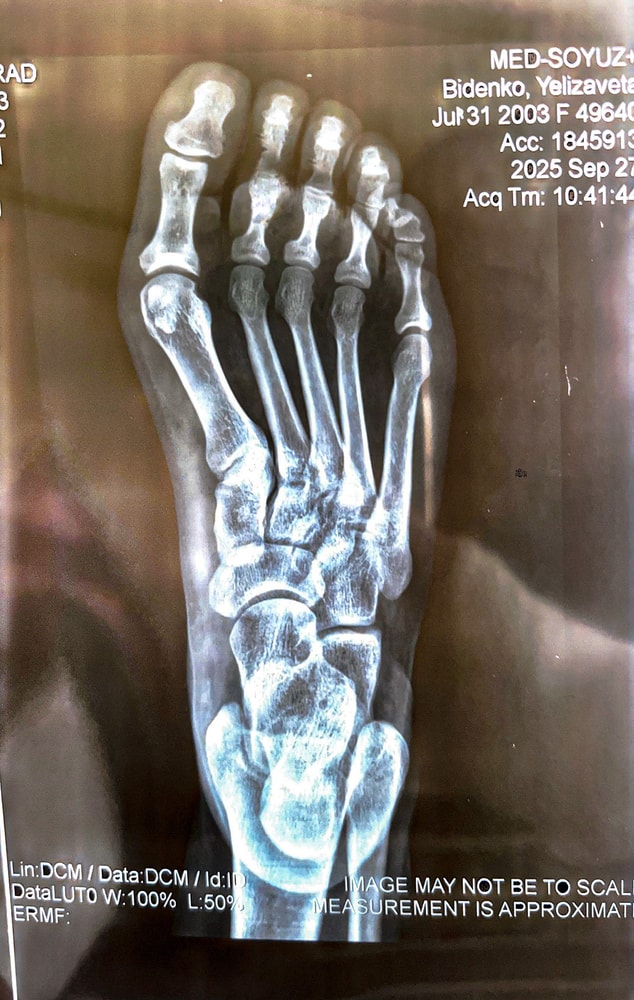

Вопрос больше по ортопедии

Если ли тут трещина 2,3 палец ?? Очень сильно опухло , гематома ступать больно . А к врачу в понедельник. Травмпункт ужасный

27.09.2025